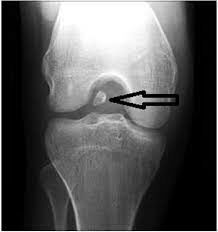

5.有關膝關節攝影呈現intercondylar notch的敘述,下列何者錯誤?

(A)可以呈現膝關節的loose body

補充:A選項 loose body=游離體

關節內的游離體,也有人稱之為關節鼠。當人體的關節出現退化或損傷,關節內會有組織碎片脫落,這些組織可能有纖維或軟骨組成,當病人在活動時這些組織碎片會在關節腔內移動,影響關節活動。症狀包括關節卡住的感覺、關節疼痛、腫脹、僵硬,有些人甚至能摸到游離體。

初步診斷可先觀察病人的症狀,有時觸診就能發現游離體,之後可做影像學檢查如X光、關節鏡或核磁共振。治療上不論大小游離體都建議以手術移除,因為游離體可能影響關節內的軟骨,近年多用微創手術治療,通常療程結束後一周左右病人就能恢復正常行走。